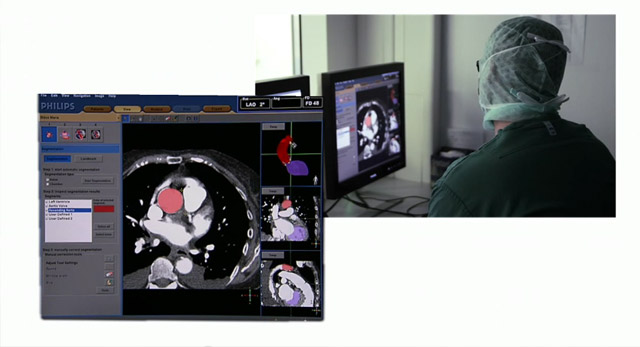

يتطلّب التعرّف الدقيق على هياكل القلب وفقًا للصور الطبية سنوات من التدريب والخبرة.

يمكن أن يشكل استخدام الأشعة السينية وتقنيات التصوير ثلاثي الأبعاد بالموجات فوق الصوتية وتفسيرها أثناء إجراءات علاج أمراض القلب الهيكلية (SHD) تحديًا، وخاصة عند توجيه مسابر القسطرة التي تحمل الأجسام المزروعة.

وبالتالي، يساعد الوصول السهل والسريع إلى الرؤية المحسنة والتنقل عبر المقاطع التشريحية للأنسجة الرخوة باستخدام التوجيه بالصور المباشرة في تحديد المسار الأمثل للعلاج بعد التوصل إلى التشخيص الصحيح الموثوق.

الرؤية الذكية والتنقل في الوقت الفعلي.

يجمع جهاز EchoNavigator بين التوجيه بالأشعة السينية المباشرة وتخطيط الصدى ثلاثي الأبعاد في إجراءات إصلاح أمراض القلب الهيكلية (SHD)، مما يمنح مزيدًا من الثقة عند التشريح واستهداف الأجهزة، ويحسّن فعالية الإجراءات التداخلية.